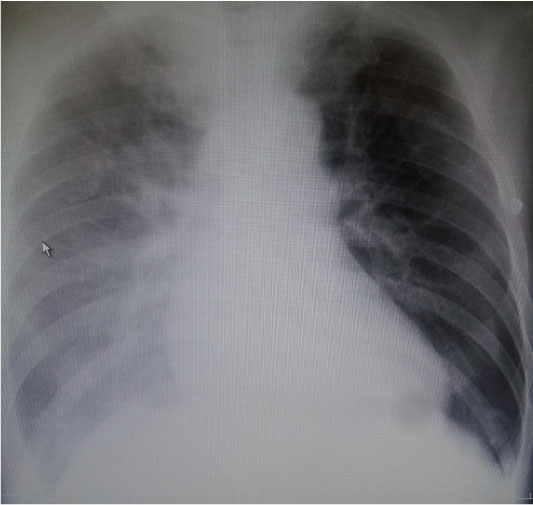

胸部Xp(臥位):右肺胸水